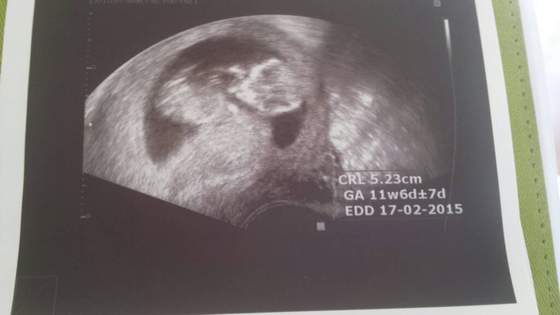

Zapomnialam napisac. Moj dzidzius ma juz 5.5 cm jest o tydzien wiekszy wg usg i tym sposobem termin porodu wychodzi mi 17.02 :-) a Prezesa rodzilam 18.02 hihi. Wszystko dobrze mis sobie spal. W przyszla srode mam prenatalne usg :-)